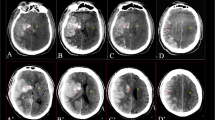

All regions of interest (ROIs) were determined using ITK-SNAP 3.6.0 [31]. One radiologist (reader A, with 6 years of experience in diagnostic neuroradiology and blinded to the ultimate diagnosis) manually segmented the images along the intraparenchymal areas of the hyperattenuation contour on each transverse section (Fig. 1). Referring to a guideline of selecting and reporting intraclass correlation coefficients (ICCs) for reliability research [32], thirty lesions were randomly selected to evaluate the intraobserver and interobserver agreement of feature extraction. The 30 lesions were re-segmented by reader A 1 month later to evaluate the intraobserver agreement. A senior radiologist (reader B, with more than 10 years of experience in diagnostic neuroradiology, also blinded to the ultimate diagnosis) re-segmented the 30 lesions to evaluate the interobserver agreement. Intraclass and interclass ICCs were used to determine the intraobserver and interobserver agreement of feature extraction. Any ICCs larger than 0.80 were considered to indicate good agreement.

Delineation of the hyperattenuating areas using ITK-SNAP software. a A hyperattenuating area in the left lentiform nucleus on nonenhanced CT. b Manual segmentation along the hyperattenuating area contour on the transverse section. c The ROI of the hyperattenuating area on a transverse section is displayed as the red area. d 3D ROI for the whole hyperattenuating area. 3D three-dimensional, CT computed tomography, ROI region of interest